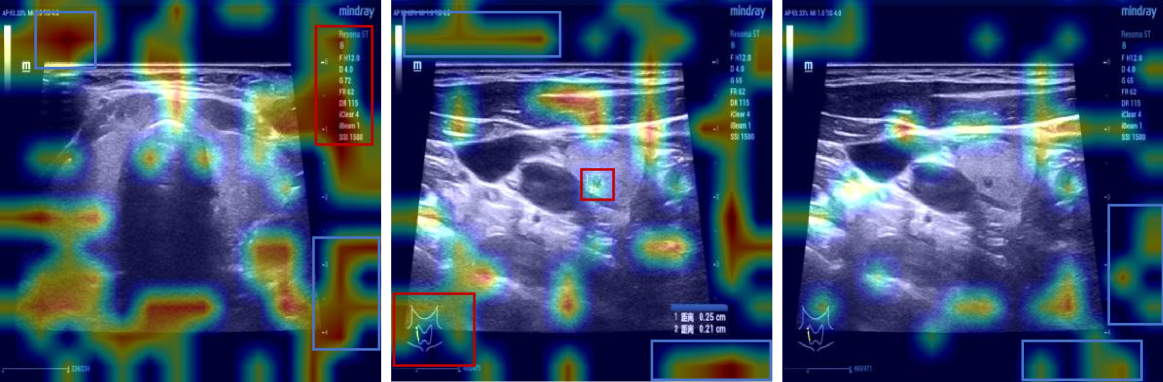

Visualization

To elucidate the internal decision-making process of VLMs, we employed the Grad-CAM heatmap visualization technique proposed by Zhang et al. (cam), where warmer regions (depicted in red) in Figure 6 indicate pixels exhibiting the strongest gradient flow towards the predicted token logit, signifying that the model primarily attends to these semantically significant regions during textual output generation, whereas cooler regions (in blue) receive negligible weight allocation, implying minimal contribution to the prediction; the visualized attention patterns confirm that the VLM’s language reasoning is grounded in semantically relevant visual features such as anatomical landmarks, quantitative measurements, and hemodynamic bar charts—highlighted within red bounding boxes—rather than spurious correlations, yet the model also exhibits attention to non-informative regions including image edges and black areas—highlighted within blue bounding boxes—which lack semantic utility, thereby highlighting a persistent challenge in VLMs: the coexistence of semantic consistency (focusing on task-critical visual elements) and spurious associations (distracting attention to noise or irrelevant artifacts); future work should enhance model robustness and interpretability through strategies such as attention regularization, constrained attention routing, and explicit mitigation of spurious associations.

Refer to caption

(a)

(b)

(c)

(d)

(e)

(f)

(g)

Figure 6: Visualization results. Red boxes highlight meaningful regions, while blue boxes indicate irrelevant or meaningless areas.